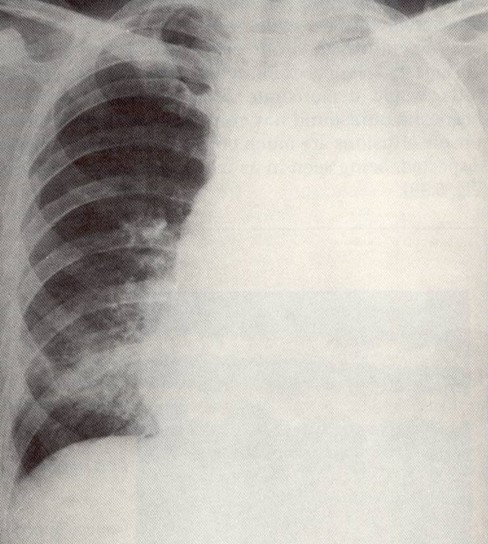

You are still practicing telemedicine. You are shown the chest x-ray and the

results of a diagnostic thoracentesis of a 45-year-old man with a long history of

joint pains.

The chest x-ray shows a large left-sided pleural effusion and a small area of

consolidation in the right lower or middle lobe (left image). A microscopic view